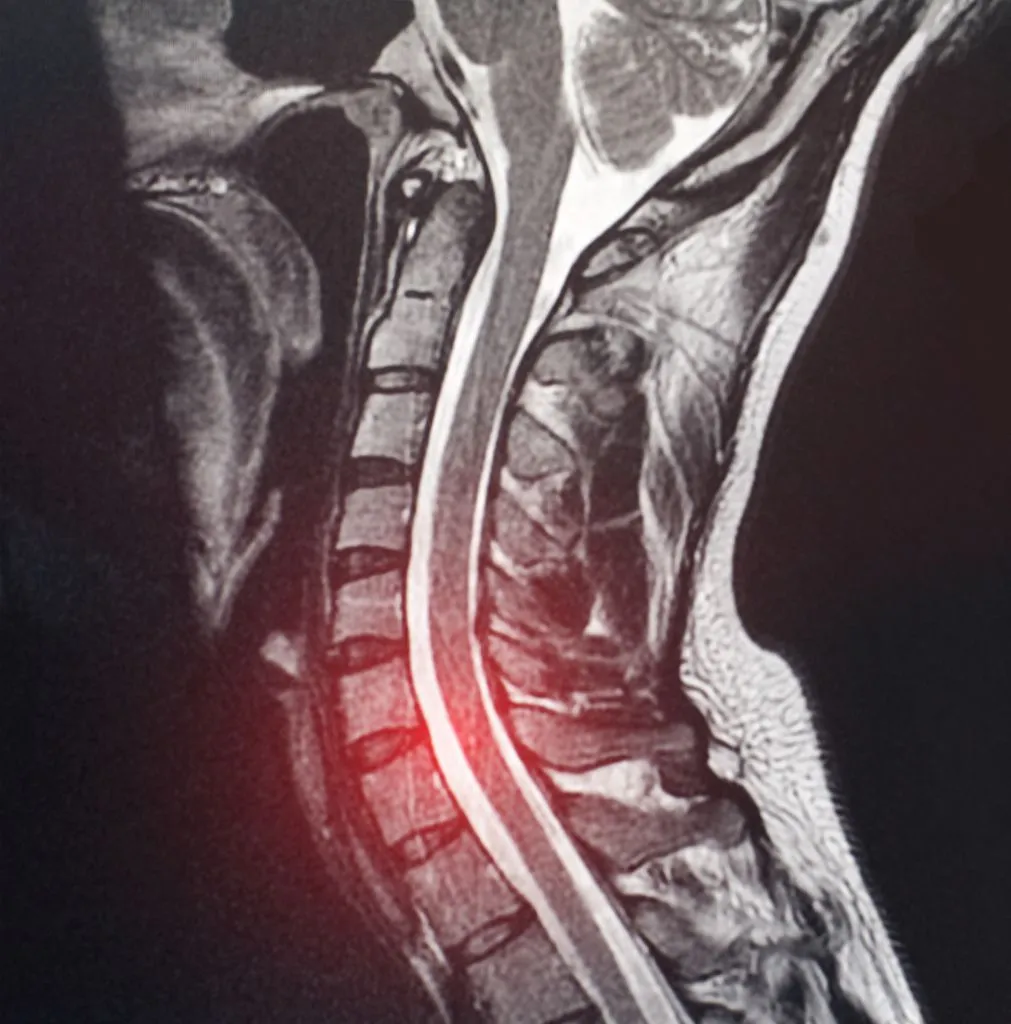

MRI: The gold standard for visualizing C7-T1 disc pathology. However, this level can be challenging to image due to shoulder overlap and the transition to the thoracic spine. Dedicated cervicothoracic junction sequences may be necessary for optimal visualization.

Two weeks post-accident, she developed severe pain radiating down the ulnar (pinky) side of her left arm, accompanied by numbness in her ring and little fingers. An MRI revealed a C7-T1 disc bulge with foraminal stenosis; the disc material had been forced laterally during the trauma, narrowing the space where her C8 nerve exits the spine.